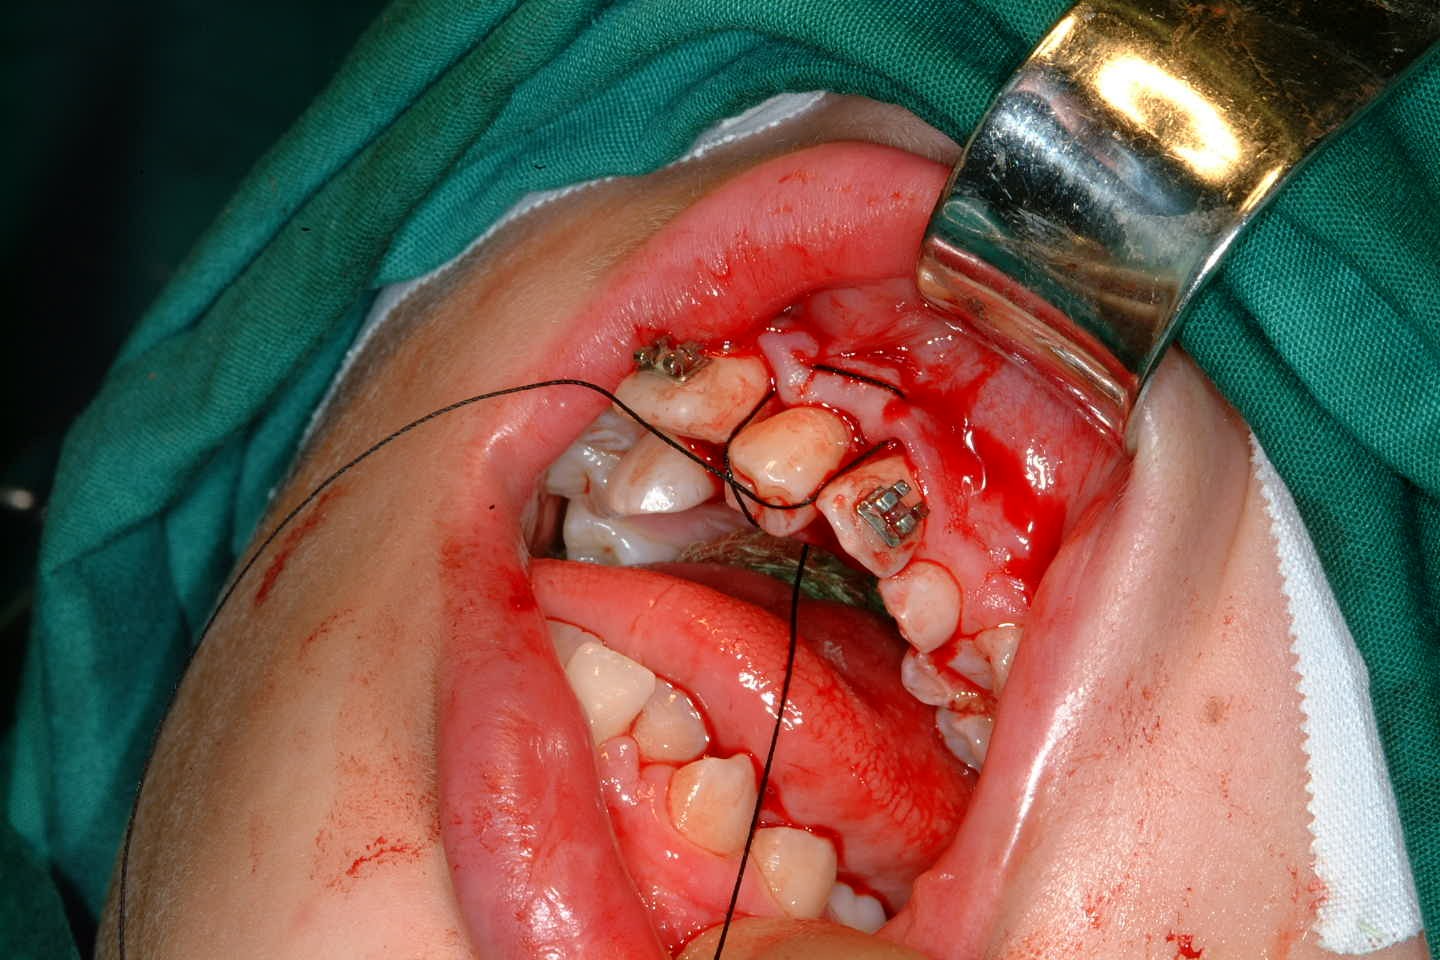

Preoperatively space is created orthodontically (Figure 22). A socket is prepared to accept the tooth using burrs with water irrigation to prevent the bone overheating and subsequent necrosis (Figure 23). If further future eruption would be beneficial (for example in a growing patient) then again, care should be taken to prevent damage to the cementum, otherwise ankylosis may occur which would prevent further eruption.

Once the tooth has been transplanted it should be splinted for between 7 and 14 days. This may be with a preformed splint cemented with a luting material or even with appropriately placed sutures (Figure 24). The area should not be disturbed during the healing phase to allow optimal healing of the periodontal ligament.